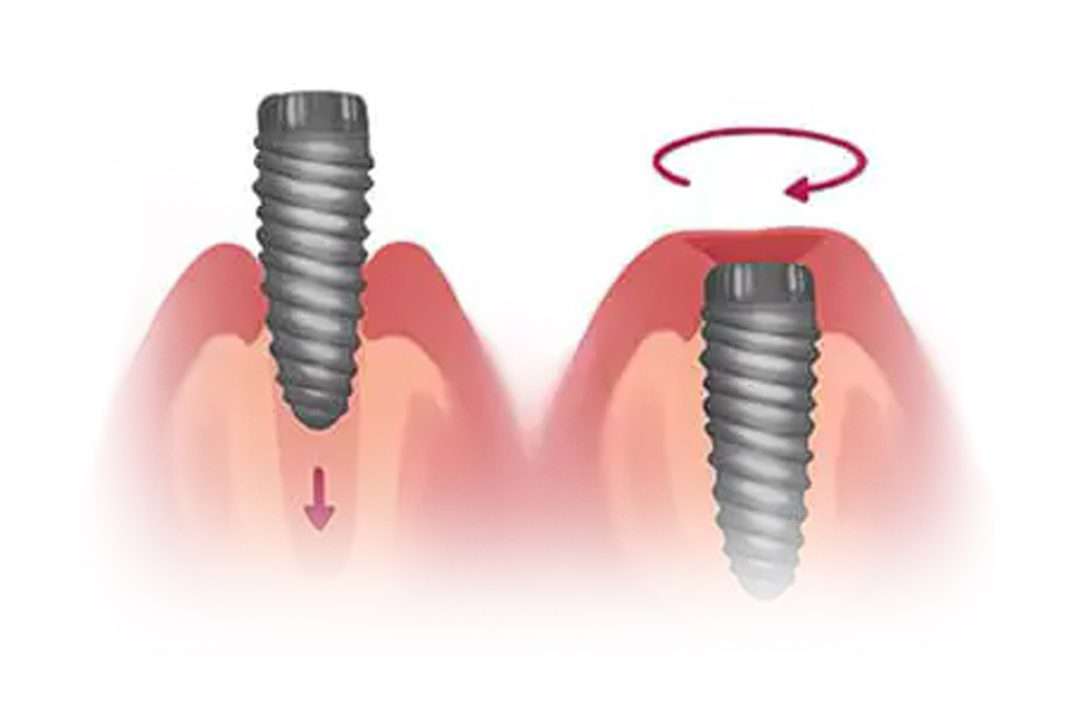

Dental implants come in many shapes and sizes but they can typically be broken down into three main parts; the crown, titanium abutment and the implant fixture. When these three parts are combined, they form the basic structure of a dental implant.

During implant surgery, the fixture of the dental implant will be inserted into the upper and/or lower jaw of the patient, this fixture will act as a replacement of a tooth’s root, bonding with surrounding bone over the course of a few months after the dental implant placement surgery.

1. Implant Placement

The implant fixture is surgically inserted into the jawbone. The fixture acts as a root for the replacement tooth.

2. Osseointegration

The implant fixture is left to recover and fuse to the surrounding jawbone.

3. Affix Abutment

The gum is reopened to expose the implant fixture in order to attach the abutment.

4. Prosthesis Placement

The final prosthesis is permanently cemented to the abutment.